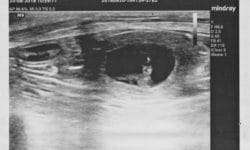

Titi na ultrazvoku ♡ / Titi on ultrasound ♡ Sedaj je tudi uradno 🙂 …. Titi je bila na UZ in prepričali smo se in videli smo, da pričakuje… Preberi več